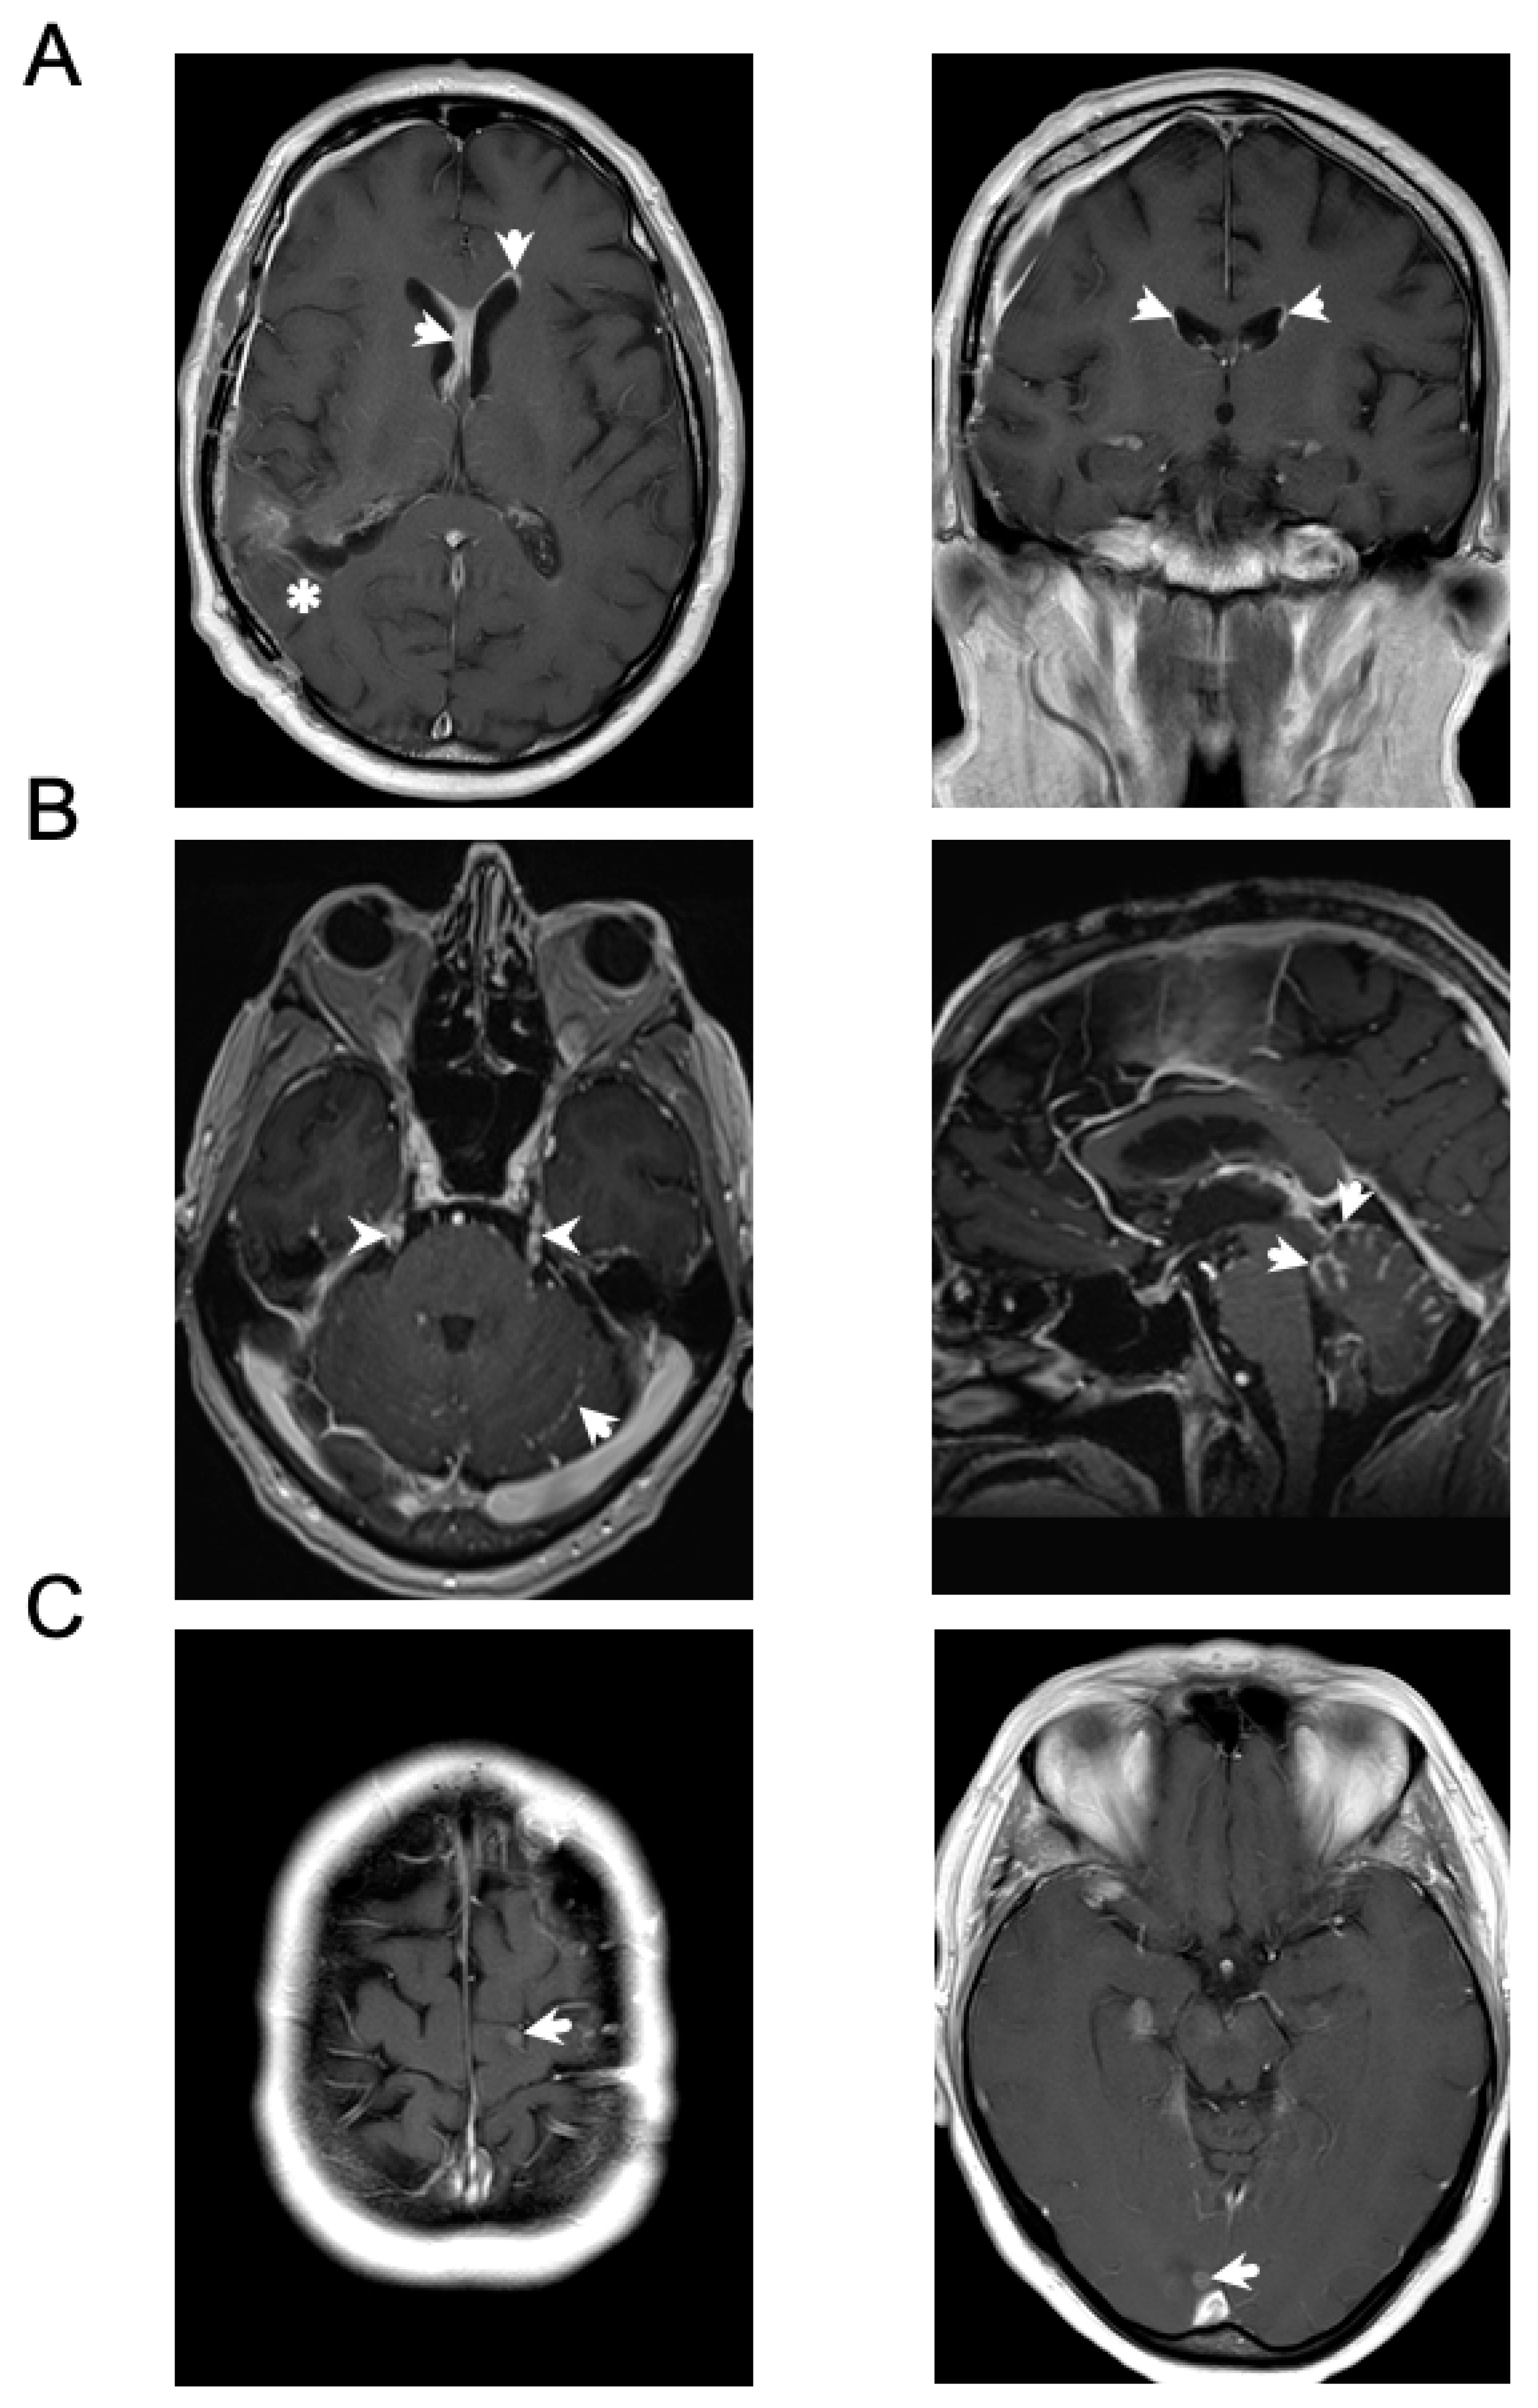

4.3. Imaging-Based Approaches